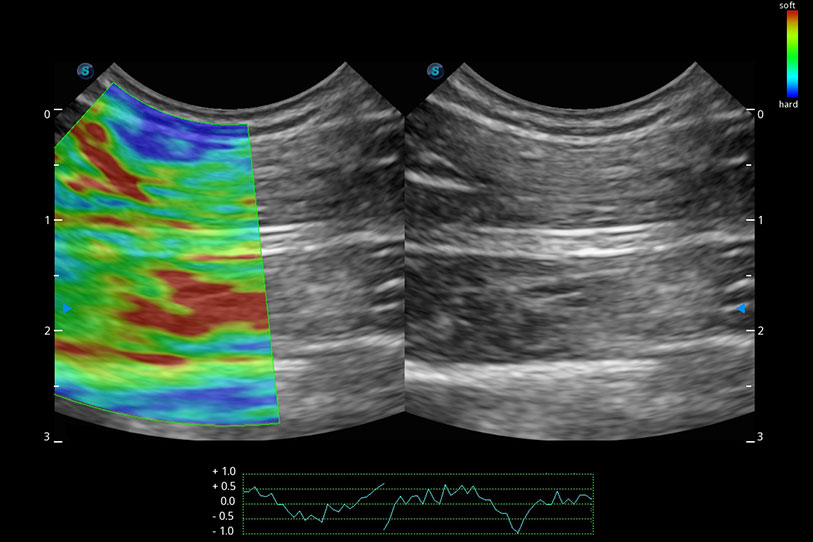

操作簡(jiǎn)便,無(wú)需高頻度外力作用即可真實(shí)反映組織的形變,快速評(píng)估腫瘤良惡性。

提供差異化的圖像風(fēng)格,使動(dòng)物醫(yī)生識(shí)別疑似病灶更容易,助力醫(yī)生篩查不漏診。